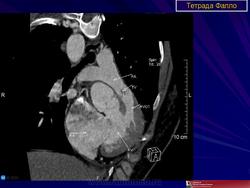

ССС. Тетрада Фалло. +

Тетрада Фалло